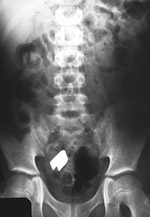

Foreign body in unsuspected location |

Whenever there is a plausible history of a foreign body ingestion, the patient should be examined from the base of the skull to the anus. The radiograph on the left shows no opaque body in the chest or stomach of an 8 year-old boy who was reported to have swallowed a foreign object. The radiologist asked for a repeat radiograph (right) to include all the abdomen and pelvis. There is a metallic tweezer in the child's distal small bowel. From Hunter, 1994 |